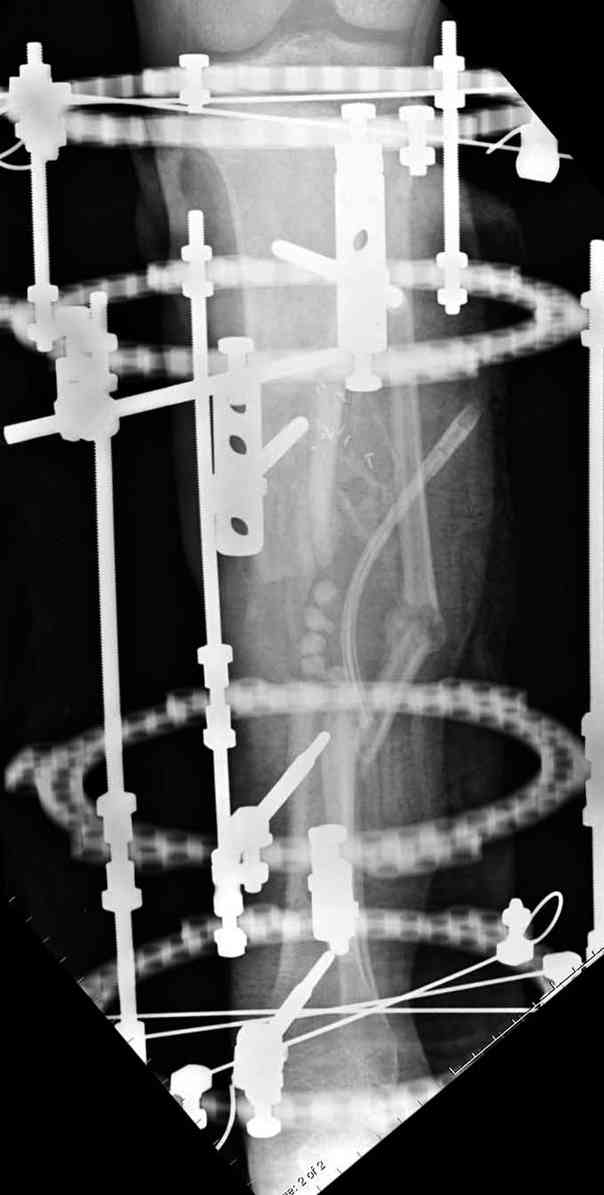

Согласен с тобой, короткий дистальный фрагмент, нет места ни для штифта, ни Т-образной пластины, да и шурупы мешают.

сделать поперечную остеотомию диафиза, полость заполнить antibiotic beads и начать удлинение.

Из аппаратов предпочтительно циркулярный, на дистальном фрагменте можно увеличить количество спиц.

Здесь случай, хотя не тот уровень, но принцип "удлинения после заполнения дефекта Antibiotic Beads" сохранен, можно немного увеличить количество бус.